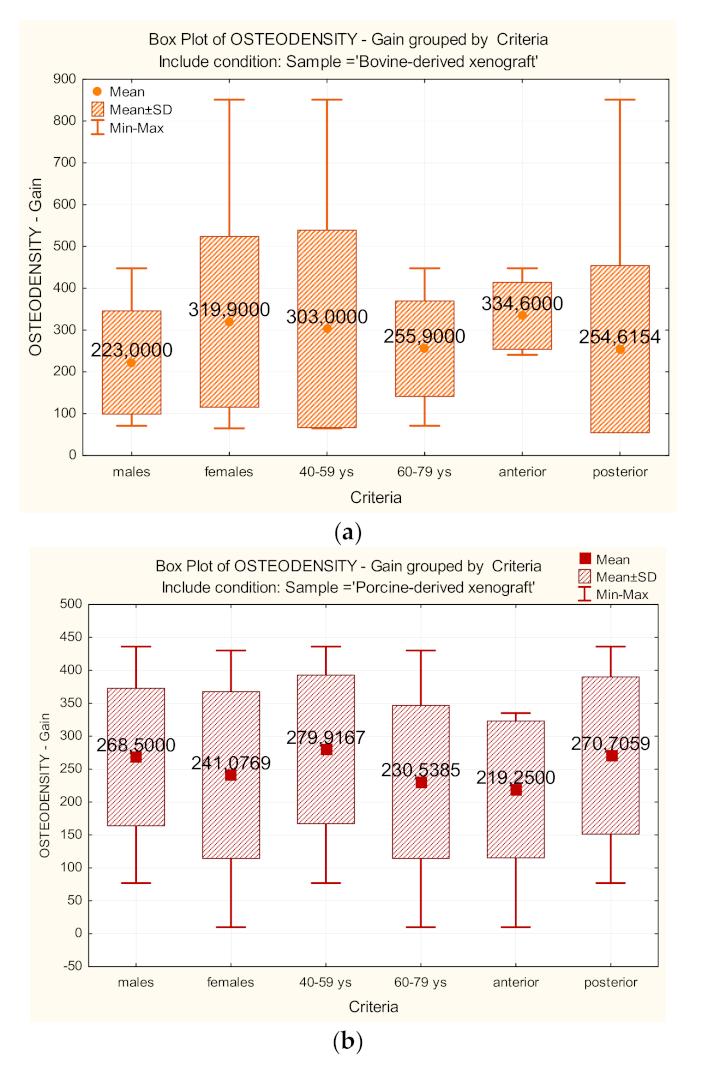

3. Results

| OSTEODENSITY– Bone gain | Control | 0.823 | 0.000 ** | 896,000 | 0.972 |

| Test | 0.964 | 0.125 | |||